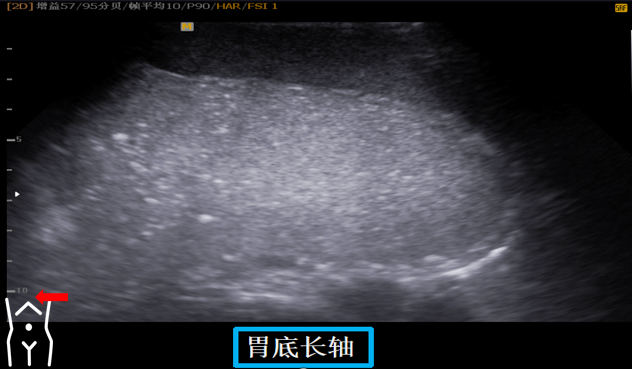

第二组胃底切面

受检者平卧或稍左卧位我们先在左肋间寻找脾以脾作为寻找胃底部界面胃底部区分是以贲门口为界限贲门以下部位就是胃底该切面为一倒C状近场与胃大弯连接远场与贲门连接在胃底切面也可以看到贲门因此我们称之为主看胃底附看贲门